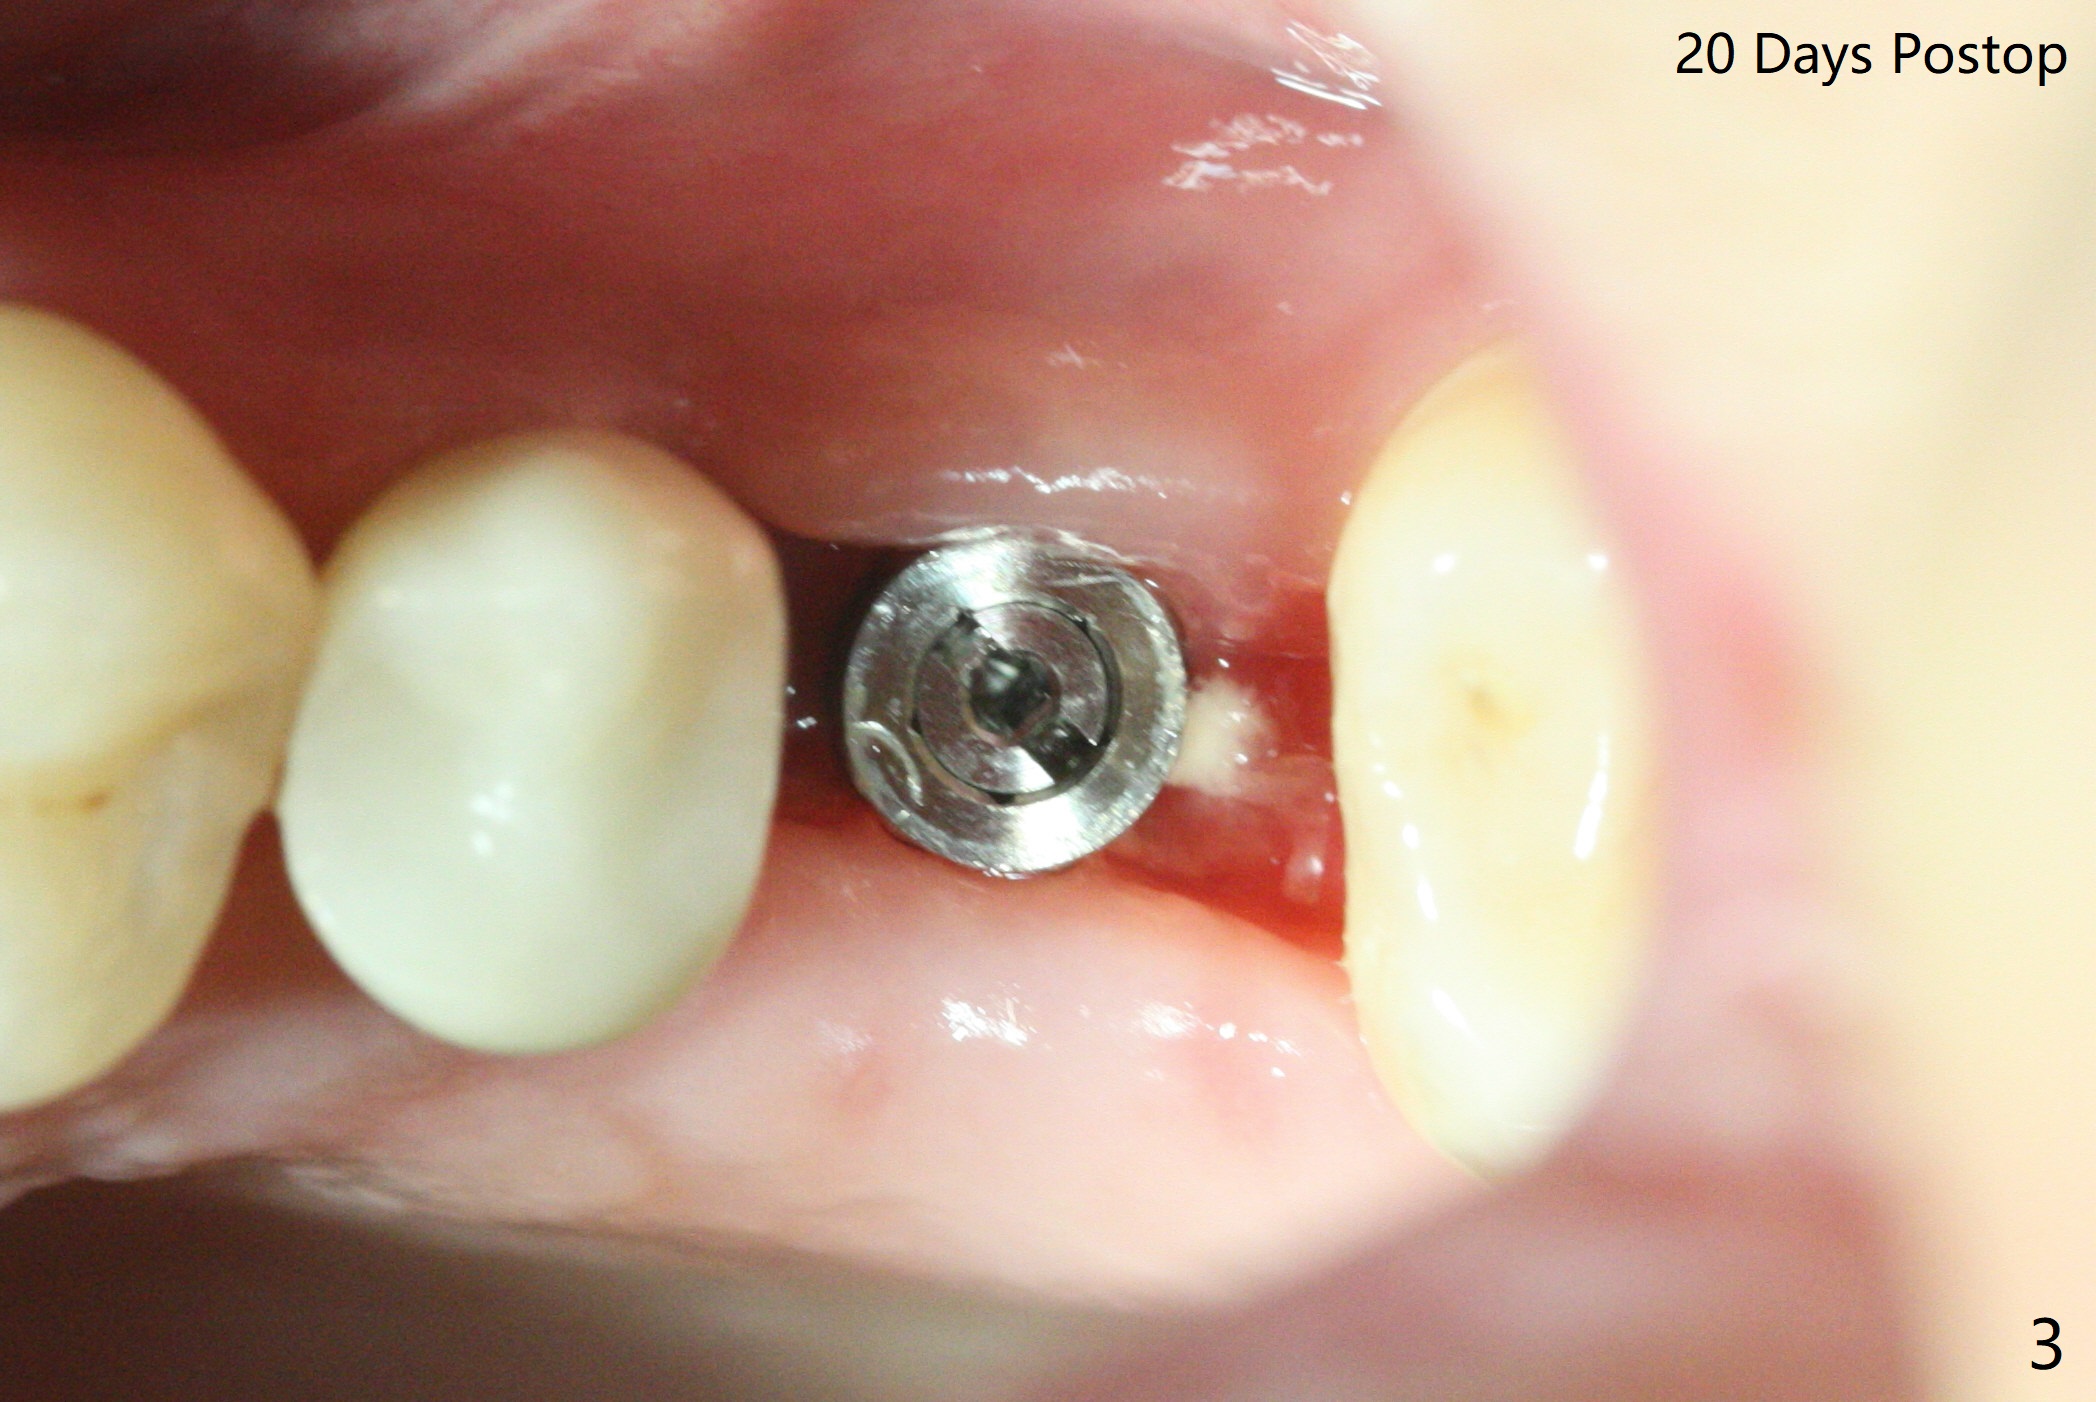

The ridge at #14 seems wide 6 months post implant removal and bone graft (before and after incision). In fact the palatal bone is low, which was the basis for periimplantitis. The new osteotomy is not initiated buccal enough. Immediate redo or guided surgery can avoid this complication. When a 4.5x14 mm tap is placed (Fig.1), the palatal threads are exposed. The buccal bone of the osteotomy has to be removed before placement of a 4.5x11 mm with 1 thread exposure palatal (Fig.2). Periimplantitis at #13 is found intraop (Fig.1 *). After removal of granulation tissue and use of Titanium brush, allograft is placed at #13 and 14 (Fig.2 ^) and is covered by PRF. Bone expansion is not conducted because of high bone density. If there is difficulty in restoration due to deep implant placement, it has to be backed up using torque wrench. The wound appears to heal by secondary intention 20 days postop (Fig.3). The implant is subgingival nearly 3 months postop (Fig.4 ^: gingival margin). It appears that the implant could be backed up (Fig.5,6). A 5 mm healing cuff is placed with Cetacaine and antibiotic ointment. The implant remains subgingival with the healing abutment 4 months postop. With Cetacaine and 2 gingival retraction cords, the implant margin is barely exposed. Large and deep gingivectomy is performed with Waterlase without too much pain. The gingival cuff is slightly erythematous and hemorrhagic on cementation (partially due to suboptimal oral hygiene, Fig.7). The margin is deep. Tatum implants are contraindicated when the gingiva is thick (Fig.8).